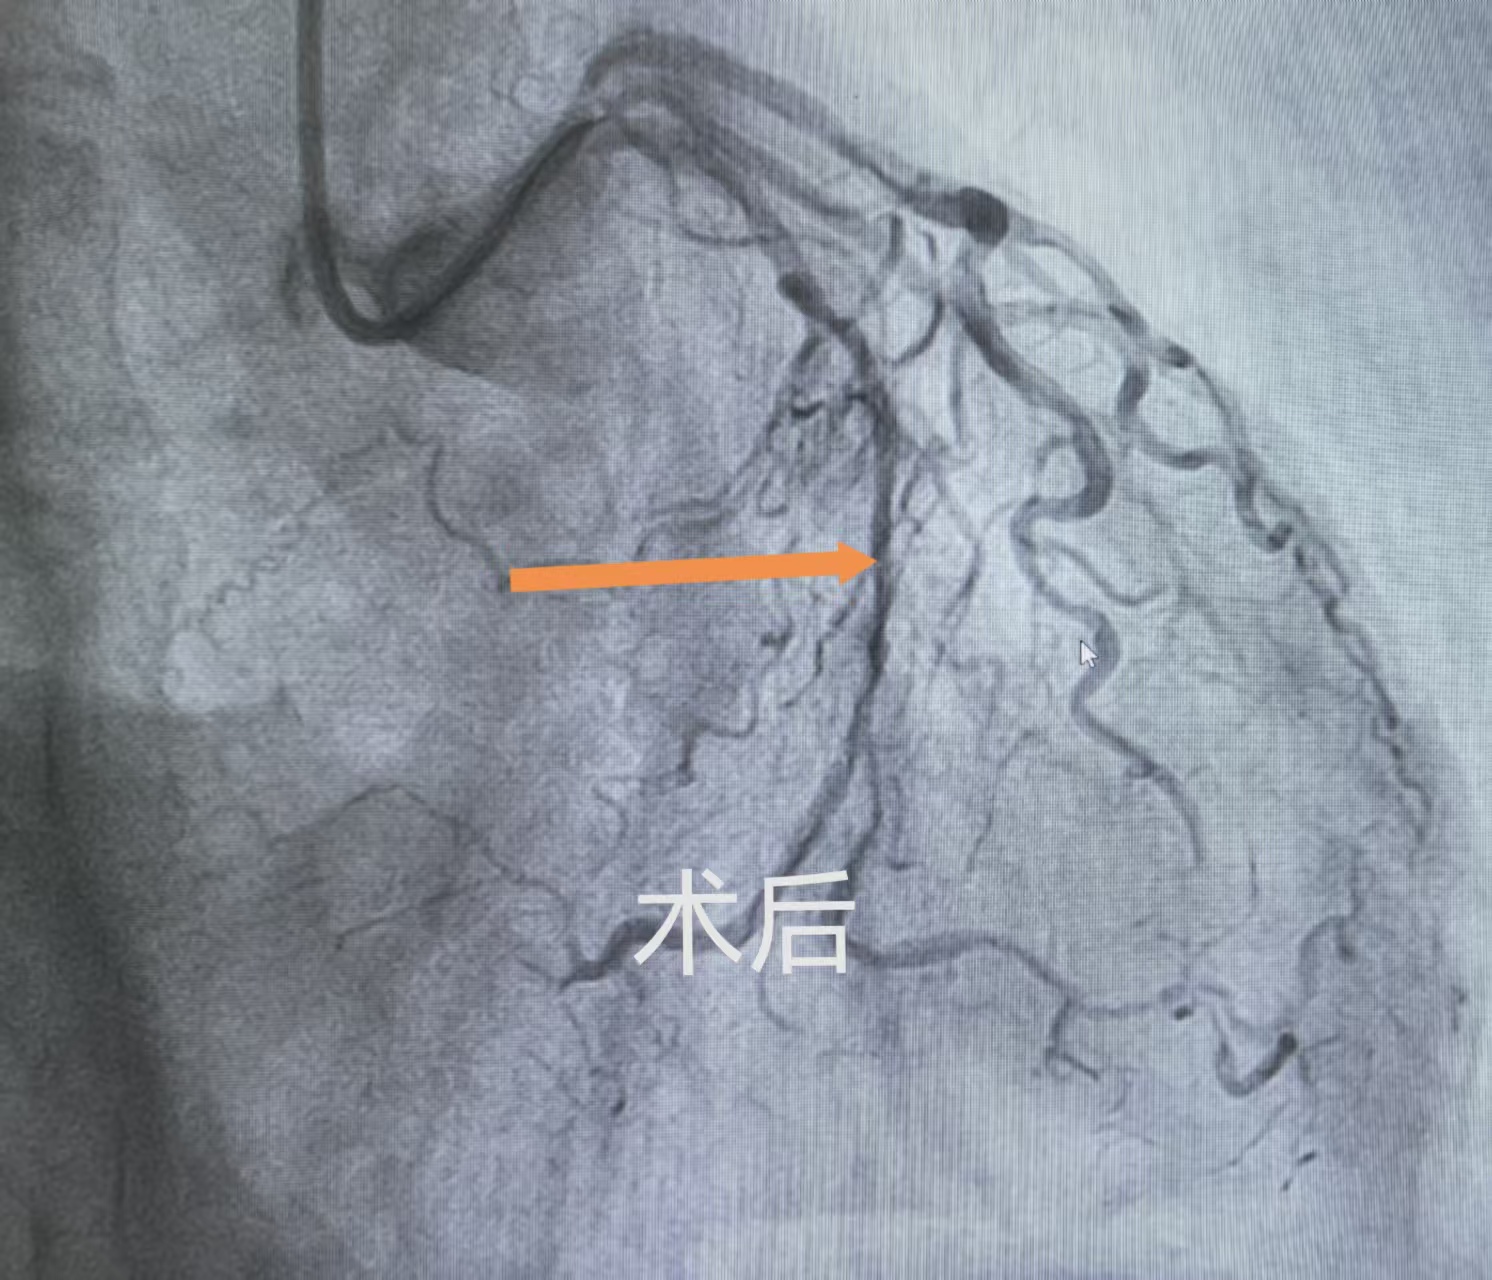

危急关头,牛锋主任带领介入团队争分夺秒,迅速敲定精准介入治疗方案。手术中,面对100%闭塞且重度钙化的血管,操作难度极大。牛锋主任凭借丰富的临床经验与精湛的操作技术,操控超滑导丝反复试探、精准穿梭,最终成功穿透回旋支闭塞端,抵达远端血管,顺利打通这条“生命通道”。随后,团队精准选用药物涂层冠脉球囊扩张血管,搭配药物洗脱支架系统支撑血管,彻底解决血管闭塞难题,让冠脉血流瞬间恢复通畅,成功化解致命危机。

术后,诊疗团队立即启动中西医结合康复方案,实现治疗效果最大化。西医介入技术快速攻克大血管“急症”,中医调理则聚焦微小血管疏通:团队在康复方案中加入通络药物,既能进一步疏通微小血管、改善冠脉微循环,提升心肌供血效率,缓解术后可能残留的轻微胸闷、乏力症状;又能抑制血管内皮炎症,降低斑块复发风险,延缓血管重构,为血管健康筑牢长期保护屏障。同时,结合李大爷“气虚血瘀”的体质,辅以益气活血中药汤剂、穴位贴敷等特色疗法,全方位调理气血,助力患者恢复。术后,李大爷胸闷症状即刻消失,精神状态快速好转,恢复情况远超预期。